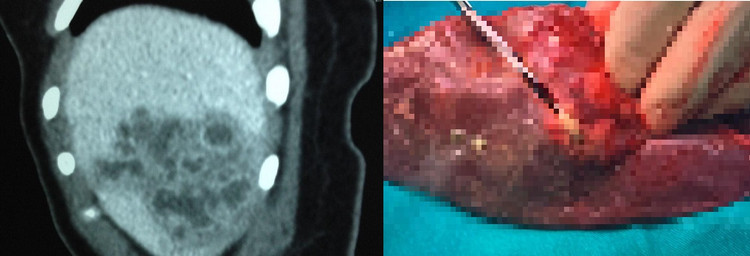

![]() |

| GS.TS Nguyễn Văn Đề thăm khám cho bệnh nhân |